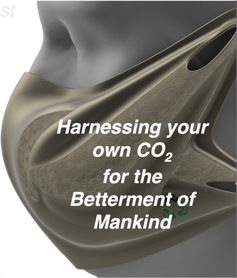

So, what is the underlying problem? LOW CO2 appears as the common irregularity among the conditions above; another 15+ conditions show the same underlying cause. The solution clearly requires a means of elevating the body's CO2 level safely, conveniently, and inexpensively. From reviewing existing Sleep Apnea research and from several of our own lab studies, we believe the single solution for multiple adverse health conditions lies with elevating the body's CO2 level. DrDave™ Smith found a clever way to accomplish this while meeting the specified requirements: The SAGE Rebreather™ mask. And here's how it works...